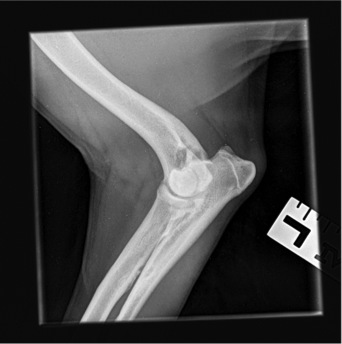

- With deterioration and lack of resolution of Charlie’s discomfort he was referred to Weighbridge Referral Centre for radiographs and evaluation of his right forelimb and cervical spine. A small osteophyte was found along the caudal border of the humeral head and there was evidence of remodeling of the medial coronoid process which could be indicative of a degree of elbow dysplasia; however, these findings did not necessarily explain the degree of pain that Charlie has been experiencing clinically. The owner reported that this week prior to our evaluation had been particularly painful for Charlie. He is currently on Metacam, but the owner does not believe that it is helping as much as it did when Charlie was initially placed on the medication.

- Radiographs: